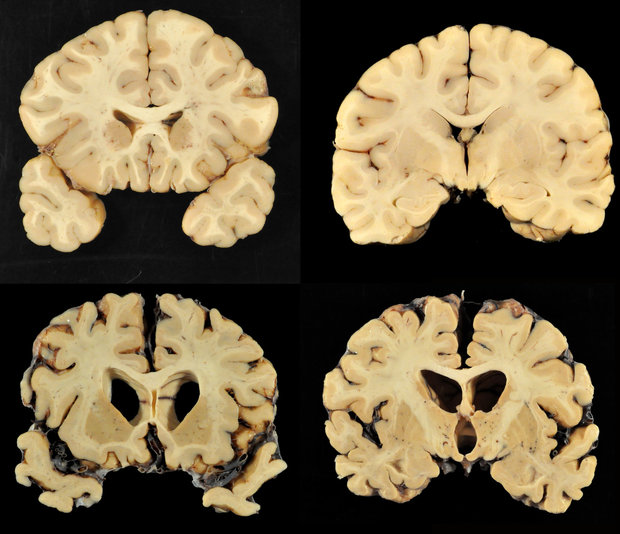

بیماری سی تی ای( مرگ تدریجی سلول های مغز بر اثر ضربه های مکرر به سر) احتمالا به دلیل ضربه های مکرر به سر به وجود می آید و افراد مبتلا به این بیماری، با گذشت زمان بدتر می شوند و نشانه هایی مانند مشکلات یادگیری، از دست دادن حافظه و افسردگی را بروز می دهند. این بیماری معمولا پس از مرگ افراد نیز قابل شناسایی است.

البته این بیماری شدت و ضعف دارد و اغلب در بازیکنان حرفه ای فوتبال و کسانی که در لیگ های حرفه ای مشغول هستند اغلب دچار سی تی ای شدید می شوند.